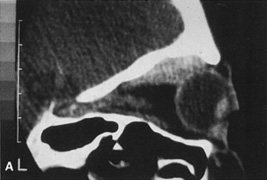

Magnetic resonance imaging is useful in selected cases, especially when evaluating the orbital cranial junction. Significant bony artifact and a lack of orbital fat in the orbital apex make CT scan resolution of the orbital apex structures poor. Because cortical bone has low signal on MRI, there is no bone artifact when viewing the orbital apex on MRI. The lack of intervening fat in the apex to provide contrast is overcome on MRI because contrast is provided by the individual nuclear characteristics of each tissue so that the orbital apex structures are visualized well. Consequently, conditions that affect the optic nerve and chiasm, such as optic nerve meningioma and glioma, generally are evaluated with MRI rather than CT scan (Fig. 2).

Fig. 2. A. Axial orbital CT scan of right optic nerve meningioma. Note lack of detail in orbital apex. B. Axial orbital MR image, same patient. Note increased detail in orbital apex owing to lack of bone artifact. C. MRI with gadolinium contrast. Note extension into brain not easily appreciated with CT scanning or MRI without contrast.